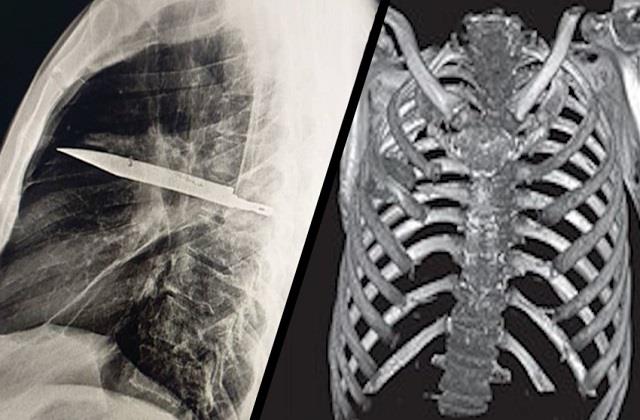

जांच के लिए जब शख्स कोअस्पताल ले जाया गया और एक्स-रे किया गया, तो रिपोर्ट देखकर डॉक्टर भी दंग रह गए। तस्वीर में साफ दिखा कि उसके सीने के भीतर धातु का टुकड़ा फंसा हुआ है। डॉक्टरों ने बताया कि इतने लंबे समय तक किसी व्यक्ति के शरीर में चाकू का ब्लेड रहना और वह जिंदा रहना बहुत ही दुर्लभ है। आमतौर पर ऐसी चोटें जानलेवा साबित होती हैं, लेकिन यह शख्स 8 साल तक सामान्य जीवन जीता रहा।

मरीज ने बताया कि आठ साल पहले एक लड़ाई के दौरान उसके सीने में चाकू लगा था, तब उसने सोचा था कि चाकू बाहर निकल गया है, क्योंकि घाव ठीक हो गया था और उसे कोई खास परेशानी भी नहीं हुई। डॉक्टरों की मानें तो चाकू का ब्लेड पूरी तरह से उसके शरीर में घुस गया था, लेकिन वह किसी भी महत्वपूर्ण अंग को नुकसान पहुंचाए बिना त्वचा के नीचे बना रहा। तुरंत ऑपरेशन कर शख्स के सीने से ब्लेड निकाला गया। सफल सर्जरी के बाद अब मरीज खतरे से बाहर है। डॉक्टरों का कहना है कि यह केस मेडिकल इतिहास में एक अनोखी घटना है।